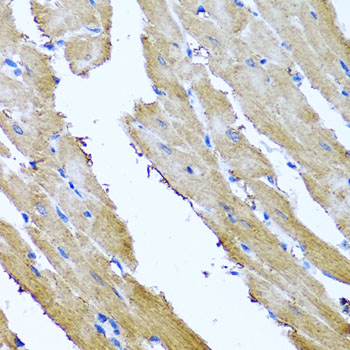

Immunohistochemistry of paraffin-embedded rat heart using SRI at dilution of 1:100 (40x lens).

Immunohistochemistry of paraffin-embedded mouse heart using SRI at dilution of 1:100 (40x lens).